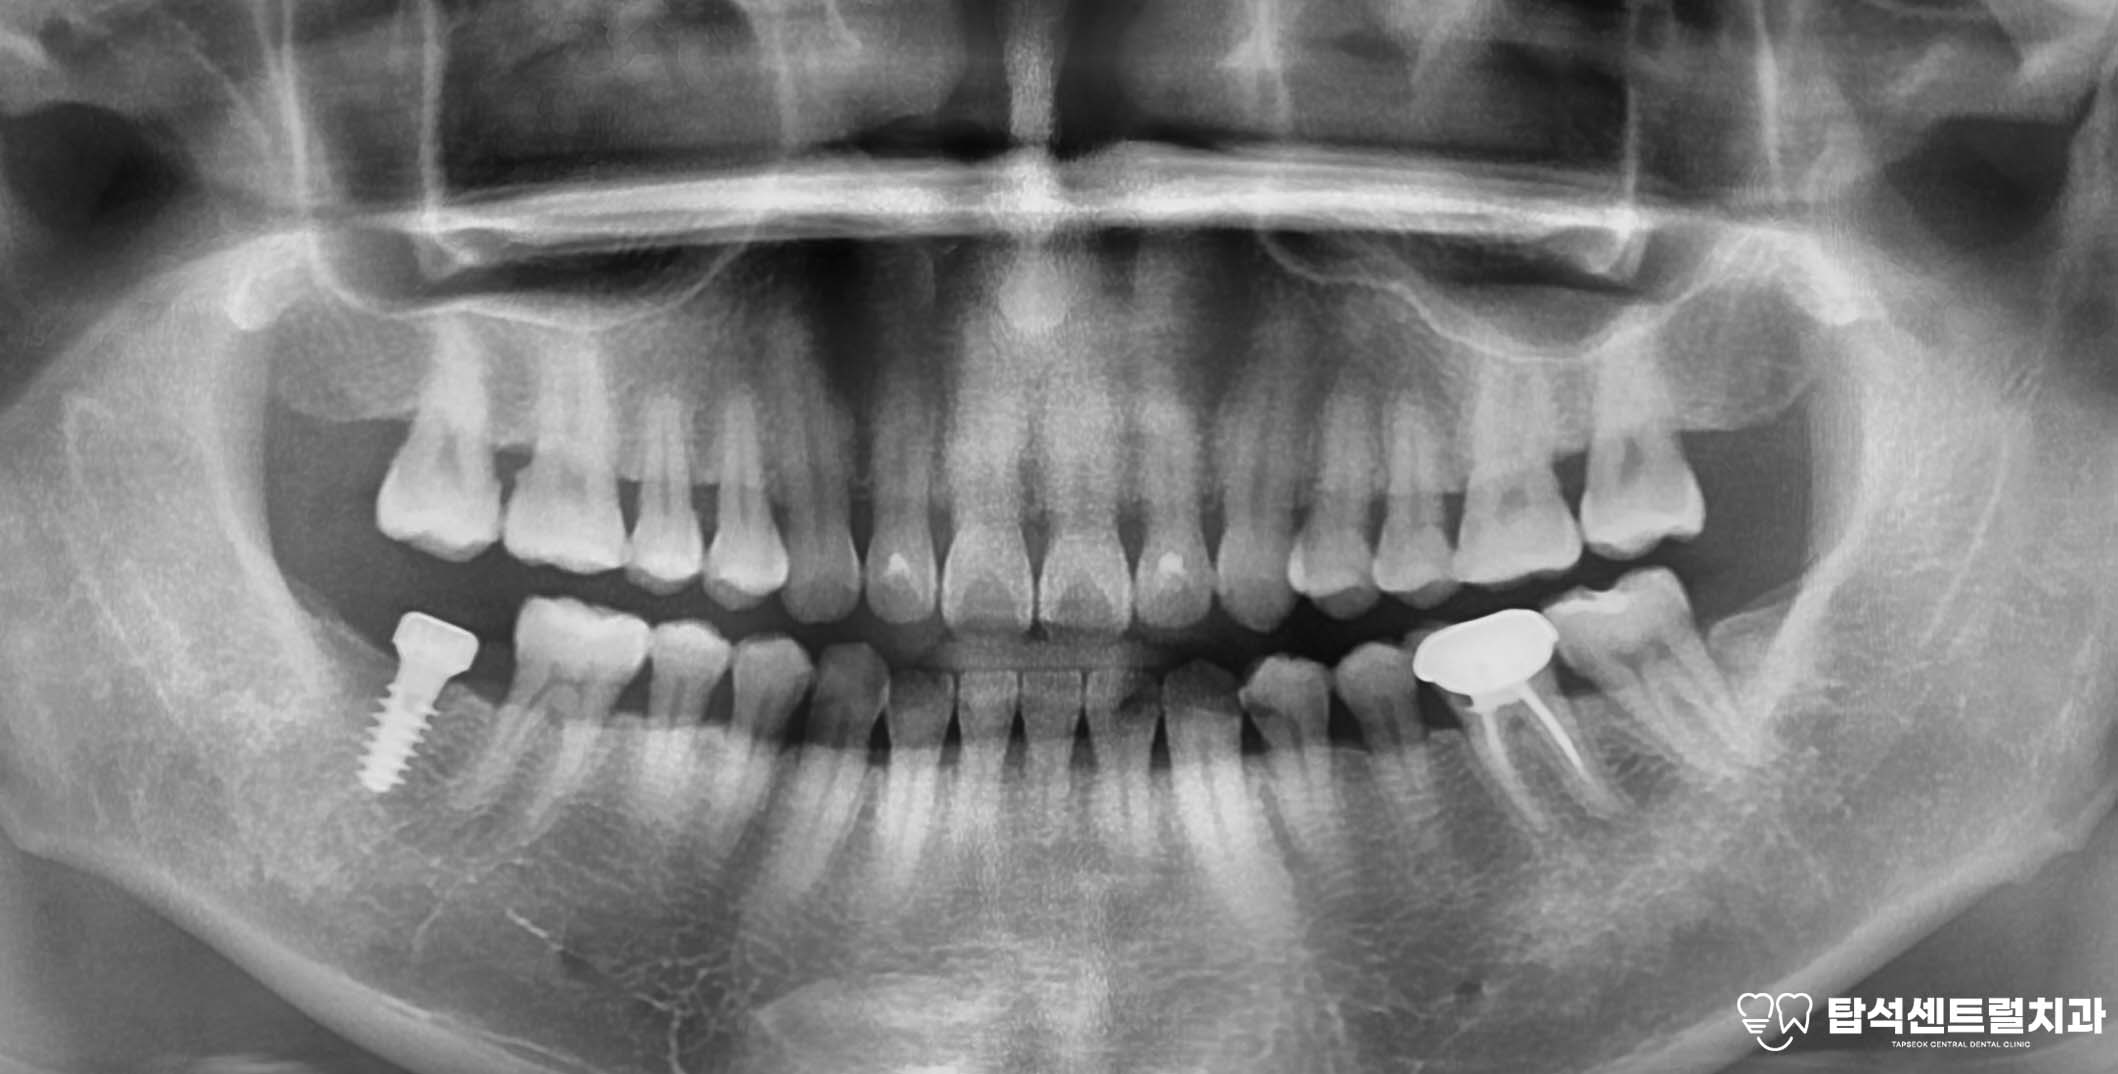

구강 검진과 문진만으로는

치아 자체의 이상이 발견되지 않을 때

엑스레이 촬영을 통해 주변 구조물을

함께 확인하게 됩니다.

엑스레이에서 의심 소견이 보이면

CT 촬영을 추가로 진행하여

상악동 내부 상태를 정밀하게 살펴봅니다.

이번 의정부 치과 에서 소개해드린

케이스의 경우에는, 아래턱에

임플란트를 식립할 예정입니다.

잇몸뼈의 상태를 확인한 모습입니다.

잇몸 뼈가 남아 있는 양에 따라,

뼈이식의 필요 유무가 정해집니다.